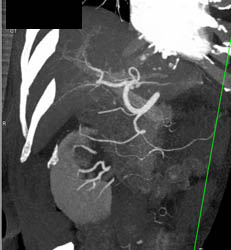

Chronic Pancreatitis